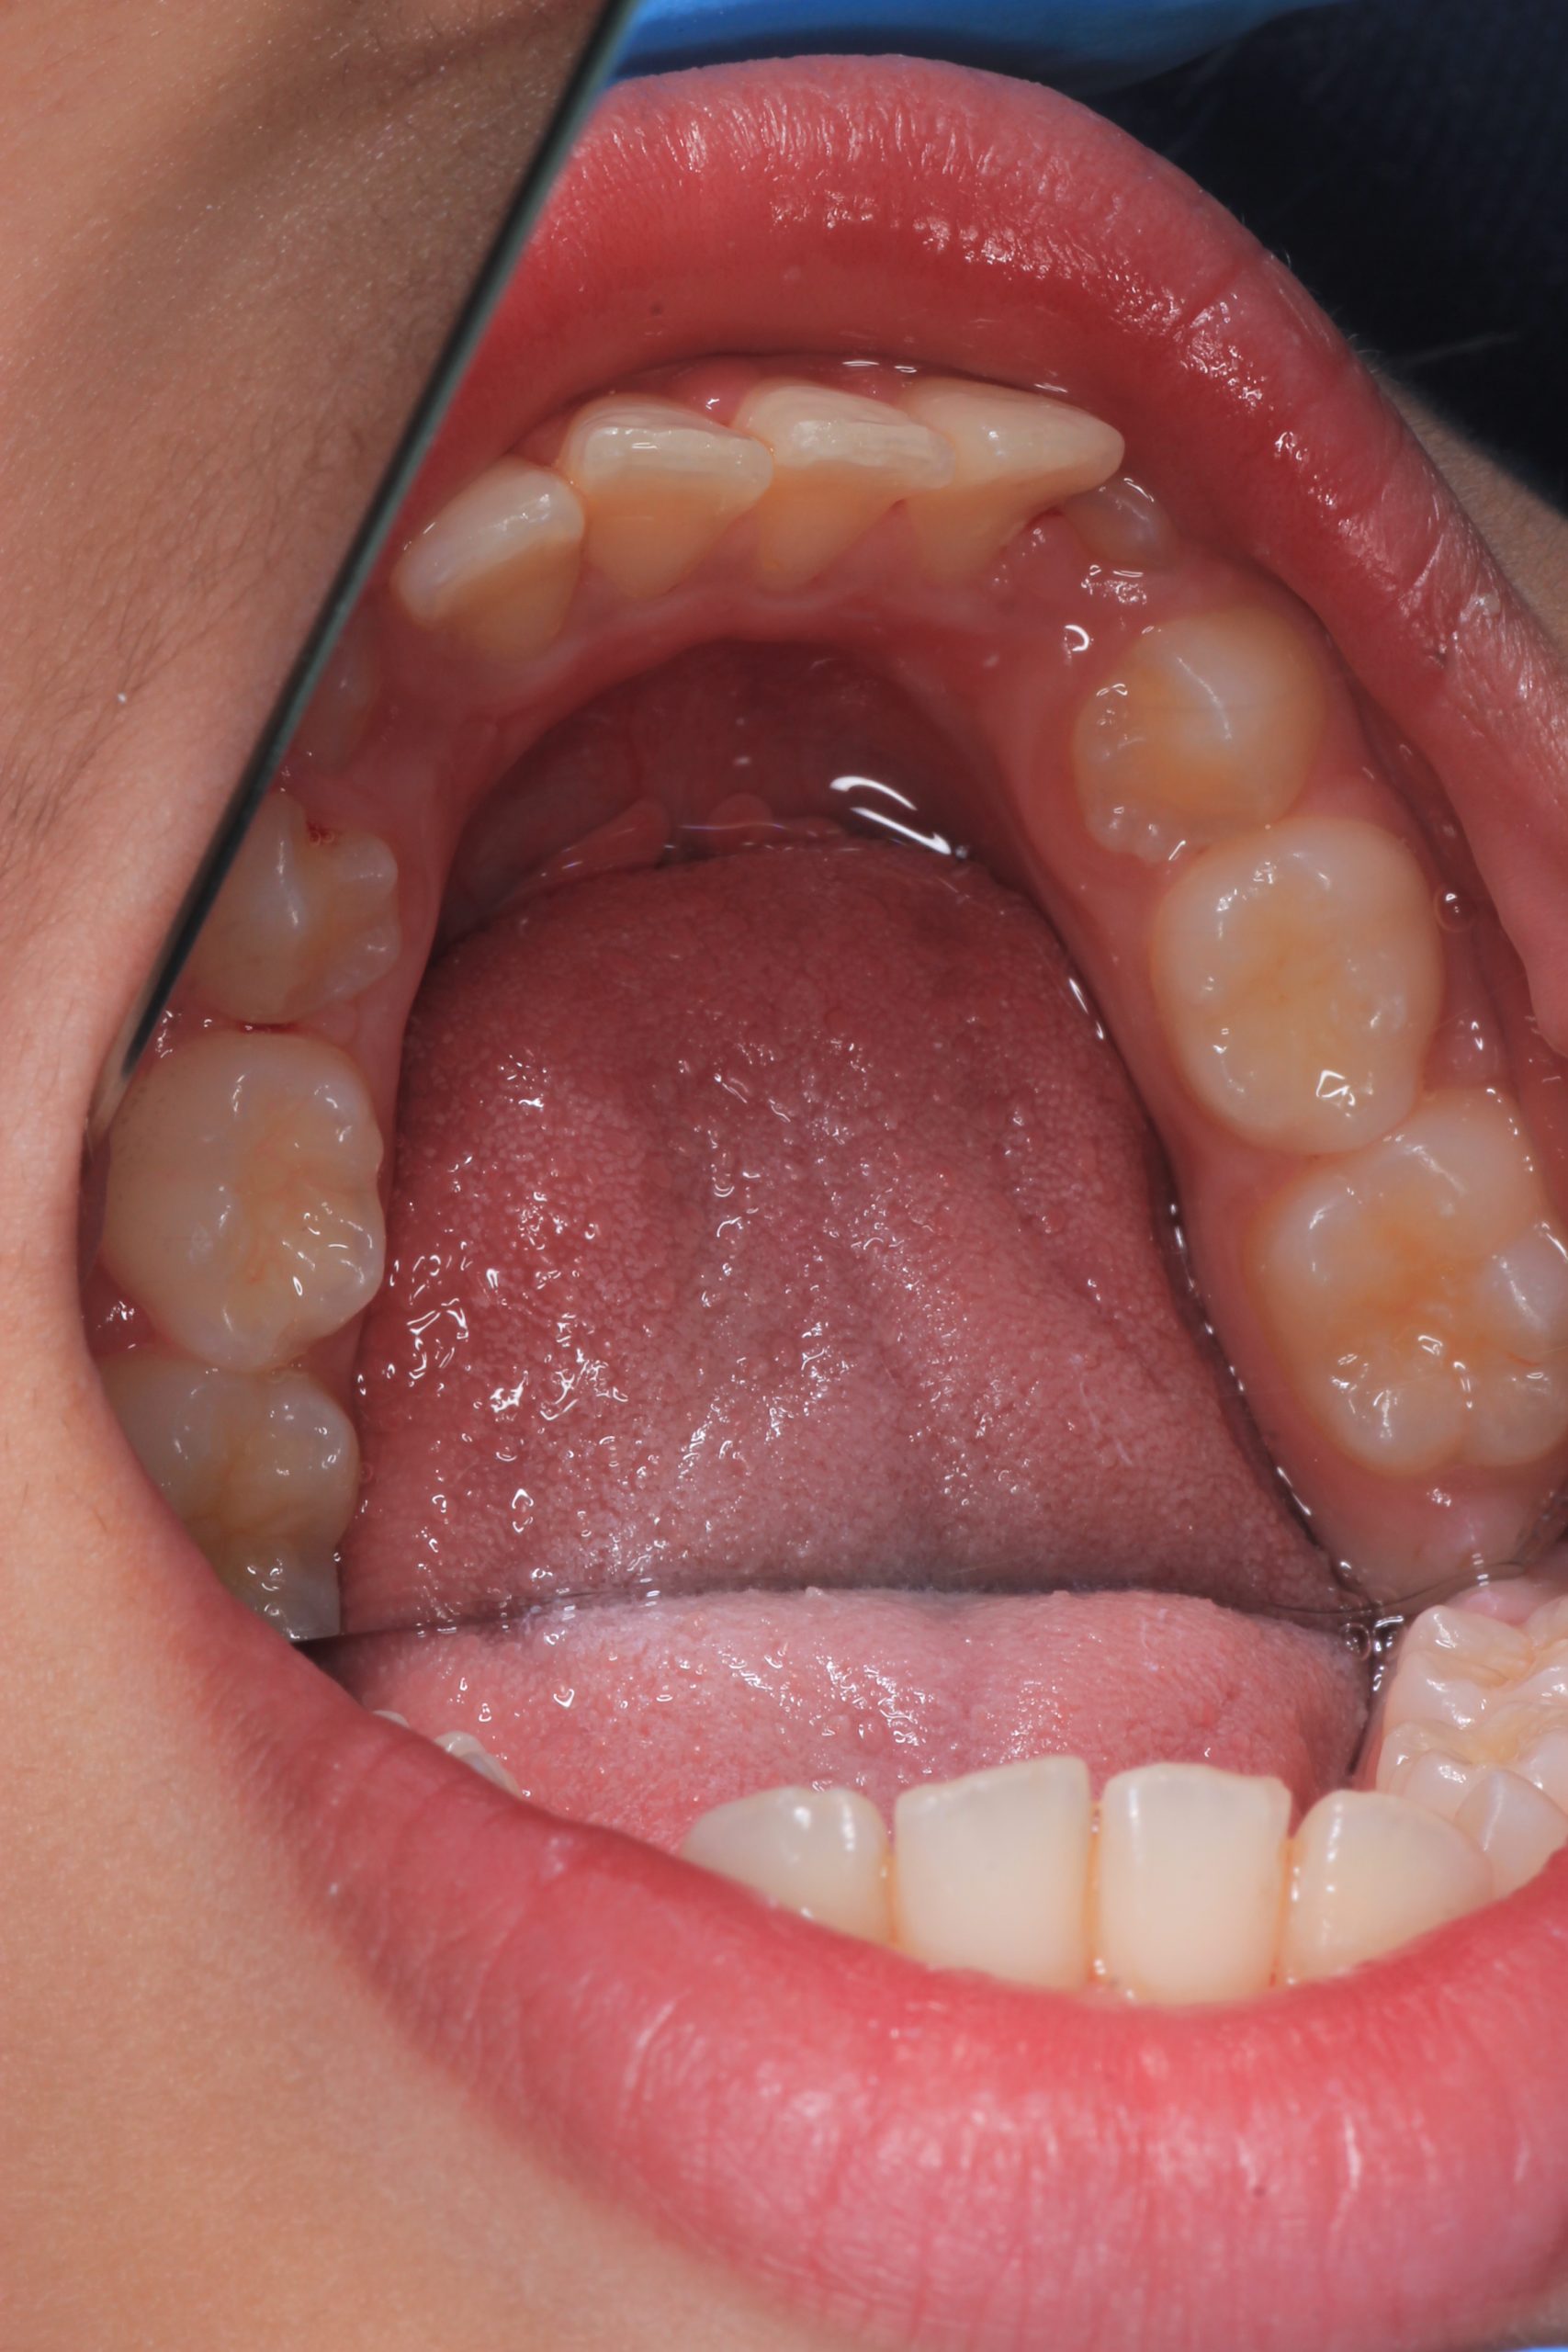

- Detailed Examination

We examine the condition of teeth, gums, and bite. - Plaque Disclosure with Special Indicators